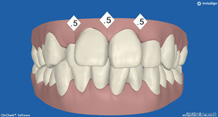

2か月後です。反対咬合は治っています。現在は正常な噛み合せになりました。

これからまだ永久歯に生え替わるので、注意深く定期的に観察していきます。生え替わった後に、また反対咬合になりこともあります。